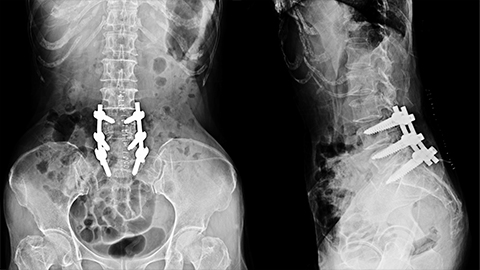

03:35 S2: Well, there are so many different directions we could go with a short discussion of this client. We could talk about what it means to donate a kidney because that's a complicated undertaking, but I think we'll make it other requests for podcasts about donating or receiving transplanted organs, so we'll hold off on that for now. Instead, let's home in on this client's history of spinal fusion surgery, and then we can also talk a little bit about massage and scar issue. I have never written or read extensively on spinal fusion surgeries, but after what I looked at today, that might change. As I dug around a little bit to gather some information for this podcast, I am finding all kinds of fascinating information about this process. For instance, spinal fusion surgeries place a piece of natural or synthetic bone and they graft it in between the vertebral bodies, and then this craft is stimulated so that the connecting bones grow and fuse all into a single unit. The goal, of course, is to maintain appropriate space between the vertebrae, so we don't have nerve pressure that generates pain, spinal fusions are done in the neck or in the lumbar spine, not usually in the thoracic spine, because of course, the ribs stabilize us there.

05:00 S2: One of the consequences of spinal fusion surgery, which is a very complicated surgery with a lot of risks and hazards involved, is that while we address those bones that are problematic and they become extremely well stabilized because essentially, they form single bones. This is gonna put an increasing demand on the joints, both above and below where the fusion is, because remember, every joint in our spine, both at the cartilaginous side on the anterior aspect and between the vertebral facets on the posterior aspect, every joint between those bones is meant to have at least a little bit of freedom of movement, and when you add up all the movement between the stepped vertebrae, of course, then we get our typical spinal range of motion, which allows us to flex and extend and side flex and rotate and all the things that we love and need to do with our spines. So this client had a fusion at L4-L5, and what this means is she probably had either a pretty severe case of degenerative disc disease that other interventions were not helping with, or she might have had another condition called Spondylolisthesis, where. You wanna say that with me? Spondylolisthesis.

06:22 S2: And in this situation, some structural changes in the lumbar vertebrae allows the vertebral body to sort of slip anteriorly, and this can create a lot of kinds of problems. People, sometimes will have a spinal fusion surgery after a really severe trauma or to treat super severe scoliosis, but most of the time it's related either to a chronic disc problem or this spondylolisthesis situation. Regardless, when we have bones in the spine that are not in the correct position, then they can exert pressure on nerve roots or on the spinal cord itself, and the results can be chronic, predictable, un-remitting pain and even loss of nerve function and loss of bladder and bowel control, if the spinal cord itself is disrupted, and obviously we would rather that didn't happen. Now, it's appropriate to try virtually every other option we can think of before settling on a spinal fusion surgery. And I think it's probably safe to say that there have been periods in time when people have taken a surgical route, maybe prematurely without trying other less invasive options that might have been more successful.

09:20 S2: However, as this massage therapist points out, she appears to have lost some of that balance that curves allow us to provide in our spine. His observation was that her lumbar curve and her kyphotic curves were completely diminished and her spine looked sort of like a tent pole rather than like the curvy spine that allows us to have shock absorption and balance. So it's not surprising with that phenomenon that she's reporting headaches and migraines, along with her chronic low back pain. This massage therapist says he gets pretty good results when he focuses on elongating her lumbar curve with sacral traction and stretching the psoas. This sounds like good strategies, as long as whatever he's doing to position her on the table doesn't threaten anything to do with her fusion, but we don't have from this information how long ago her surgery was.

11:34 S2: Guess what I found, I found a case report published by the International Journal of Therapeutic Massage and Body Work, and here's the title, The Effect of Massage Therapy After Decompression And Fusion Surgery of a Lumbar Spine, A Case Study. Of course, I will put the link to this free full text, open sourced scientific journal article, specifically about massage therapy in our show notes today, but I will let you know that in this case study, the client was a 47-year-old woman who underwent this surgery at L4-L5, just like our podcast client due to chronic disc herniation symptoms, and the goal was to see if massage therapy could help treat her pain and dysfunction that's associated with this kind of surgery. They had some success, especially around things to do with a range of motion and hamstring length. They also used a disability index to measure her sense of her ability to function, and they did some pain scores that showed some improvement in her pain scores as well, and overall they had a good experience with a limited number of massages over a specific period of time. Now, our own client's goals could be really different from the goals of the client in this published case study, but when we do a quick search for things like this, it puts us a giant step forward in figuring out how to best provide evidence-informed practice and how to not keep reinventing the wheel if we don't have to.